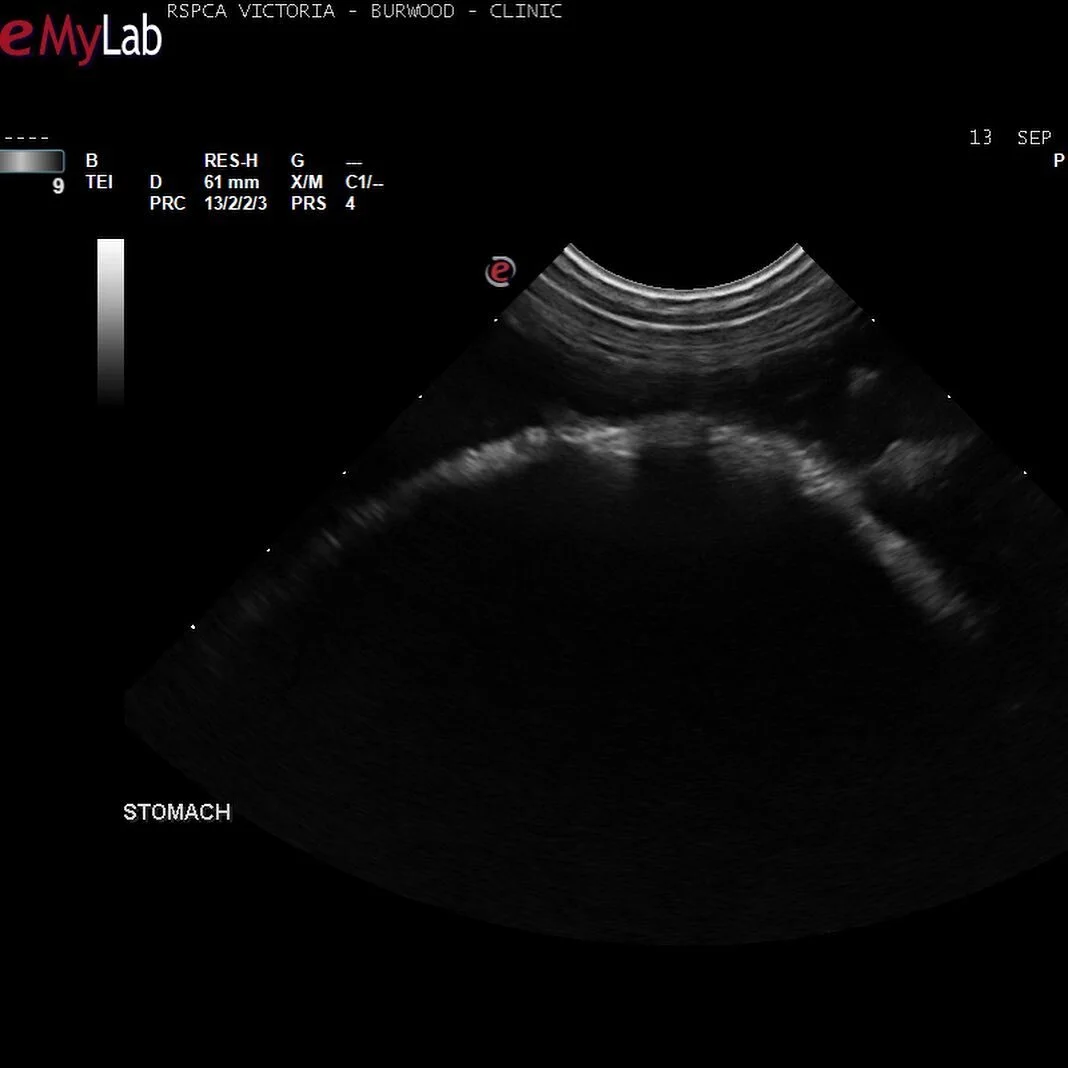

Ultrasound is an invaluable and non-invasive diagnostic test to examine the heart or organs within the abdominal cavity. During the examination, your pet will be lying on his or her side being supported by a nurse. Some patients require sedation for ultrasounds.

If your Pet has had an ultrasound or Echocardiograph, some of their fur will be clipped back to the skin. This is to allow the probe from the ultrasound to work, please see the clip examples below. The majority of patients are given a very mild sedation for ultrasound and not for echocardiograms. A slight sedation helps your pet relax during the procedure which in turn allows us to get the clearest imagine during the scan.